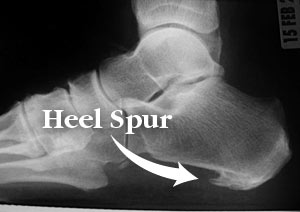

Homeopathy For Heels Pain

Homeopathy Medicines For Pain Heels (Calcaneal Spur or Plantar Fasciitis) When a foot bone is exposed to constant stress, calcium deposits build up on the bottom […]